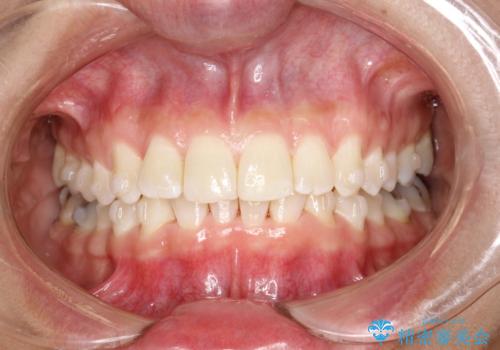

前歯のガタガタをインビザラインで矯正

- 前歯のがたつきを気にされて来院されました。

右上の前から2番目の歯が前方に大きく傾いており、下の前歯もガタガタしていました。

インビザラインにて、歯と歯のあいだをわずかに削り並べる計画としました。

しっかりとマウスピースを使用していただけたので、順調に治療を終えることができました